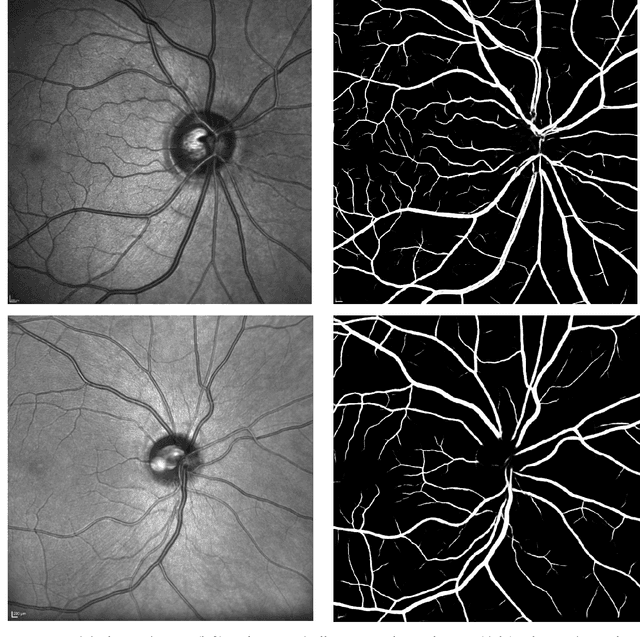

Abstract:Background and Objective: Infra-red scanning laser ophthalmoscope (IRSLO) images are akin to colour fundus photographs in displaying the posterior pole and retinal vasculature fine detail. While there are many trained networks readily available for retinal vessel segmentation in colour fundus photographs, none cater to IRSLO images. Accordingly, we aimed to develop (and release as open source) a vessel segmentation algorithm tailored specifically to IRSLO images. Materials and Methods: We used 23 expertly annotated IRSLO images from the RAVIR dataset, combined with 7 additional images annotated in-house. We trained a U-Net (convolutional neural network) to label pixels as 'vessel' or 'background'. Results: On an unseen test set (4 images), our model achieved an AUC of 0.981, and an AUPRC of 0.815. Upon thresholding, it achieved a sensitivity of 0.844, a specificity of 0.983, and an F1 score of 0.857. Conclusion: We have made our automatic segmentation algorithm publicly available and easy to use. Researchers can use the generated vessel maps to compute metrics such as fractal dimension and vessel density.